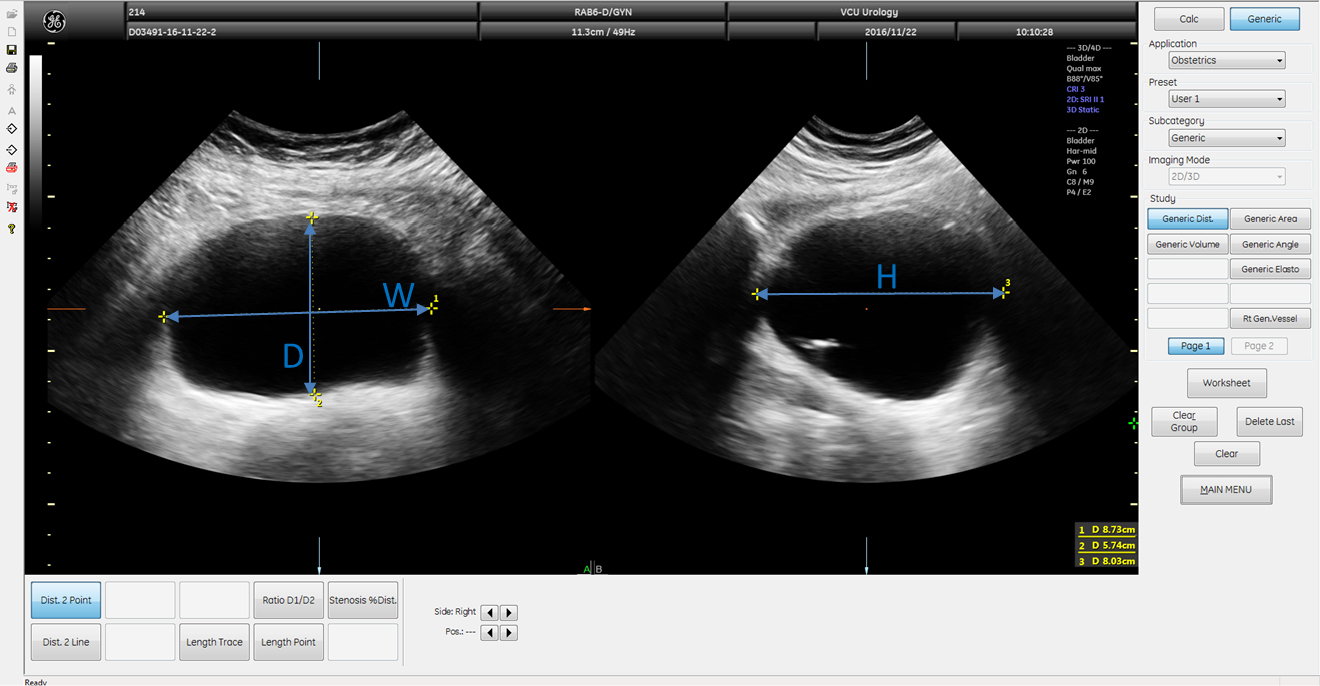

Methods: Twelve female participants with OAB completed an extended UD procedure with the addition of serial bladder ultrasound images captured once per minute. Bladder volume was measured using three ultrasound methods: (1) Vspheroid: two-dimensional (2D) method calculated assuming spheroid geometry; (2) Vbih: 2D correction method obtained by multiplying Vspheroid by a previously derived correction factor of 1.375; and (3) V3D: three-dimensional (3D) method obtained by manually tracing the bladder outline in six planes automatically reconstructed into a solid rendered volume. These volumes were compared to a control (Vcontrol) obtained by adding UD infused volume and the volume of estimated urine production.

Image calculations

???ℎ?????= ?6(?*?*?) (Eqn. 1)

???ℎ=0.72*?*?*?=1.375*???ℎ????? (Eqn. 2)